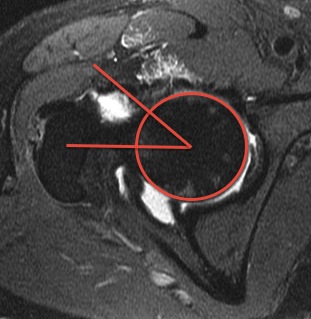

Using the axial oblique sequence, a circle is centered over femoral head. The angle is formed by:

1) A line parallel to the femoral neck axis

2) A line from the center of the femoral head to the transition of the femoral head into the femoral neck (neck radius exceeds head radius)